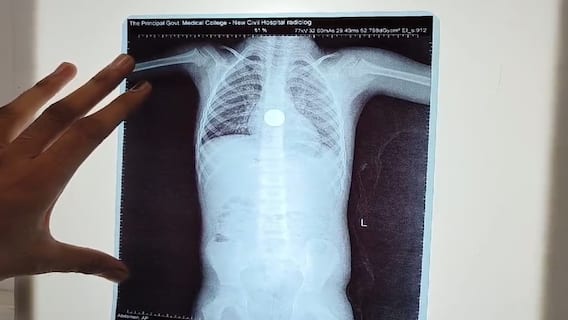

એક્સ રેમાં જોવા મળ્યો સિક્કો

બાળકને ઈમર્જન્સીમાં લાવવામાં આવ્યું હતું.  તાત્કાલિક તેનો એક્સરે કરવામાં આવ્યો હતો.  જેમાં બાળકના ફેફસાં વચ્ચેની નળીમાં સિક્કો દેખાયો હતો. જેથી તાત્કાલિક તેને ઓપરેશનમાં લેવામાં આવ્યો છે.  ઓપરેશન બાદ સિક્કો સલામત રીતે બહાર કાઢવામાં આવે તેવા પ્રયાસો હાલ તબીબી ટીમ દ્વારા કરવામાં આવી રહ્યાં છે.   જો કે, બાળકોને સિક્કા કે મોબાઈલ આપતાં પહેલા દરેક માતાપિતાએ સાવધાની દાખવવી જોઈએ.